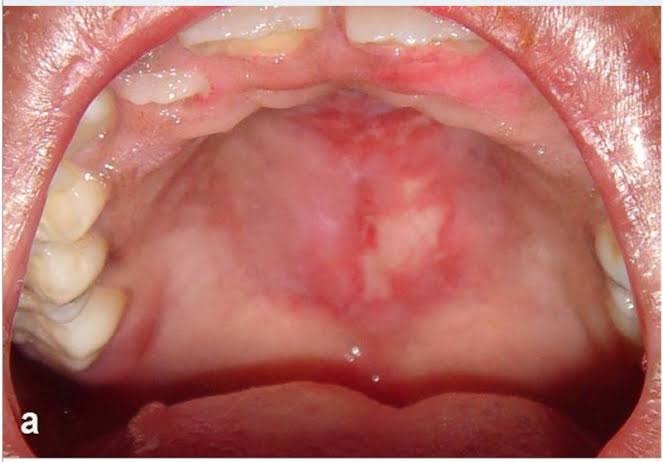

口内炎や口腔内に潰瘍がある

〈口腔潰瘍〉

口内炎や口腔潰瘍は、SLEで認める皮膚症状の一つで、0-40%程度で認めると言われています。痛みを伴わない場合も多くあります。